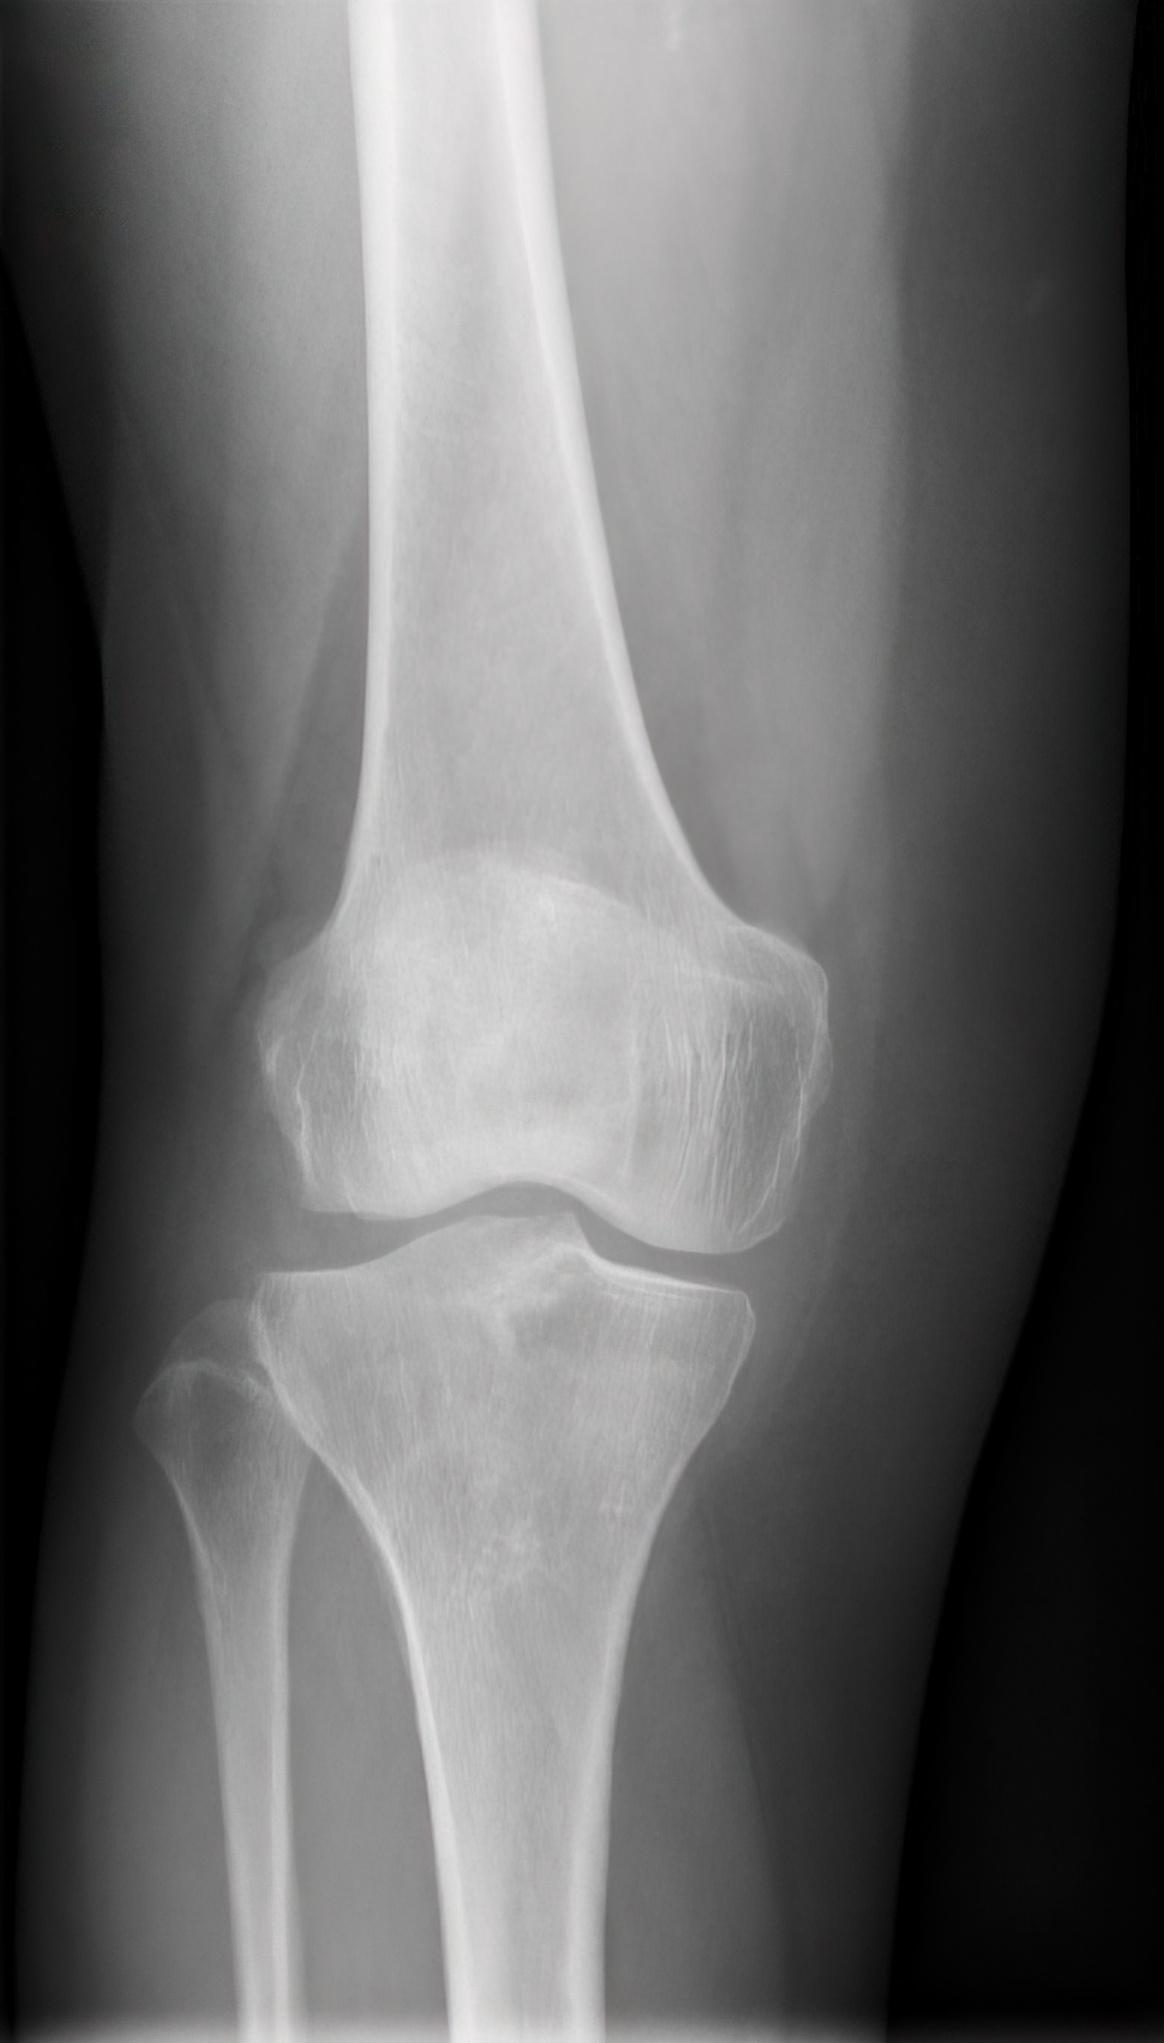

A bone fracture or broken bone, is a medical condition in which a bone is cracked or broken due to some pressure.

It can occur when there is a sudden and significant force applied to the bone, such as during a fall, an accident, or a sports injury.

Fractures can range in severity from a small crack in the bone to a complete break with bone fragments that may pierce the skin. Treatment for a bone fracture depends on the severity and location of the break, but may include immobilization with a cast or splint, surgery, or Physiotherapy in Manchester and Stockport.

A comminuted fracture is typically diagnosed using X-rays or other imaging tests. In some cases, surgery may be required to realign the bone fragments and stabilize them with pins and plates.